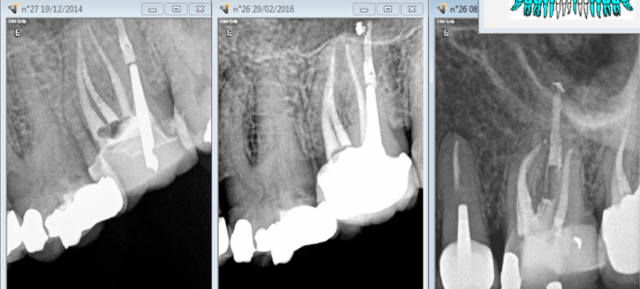

perso j'aime pas trop l'idée de faire le devis avant mon endo, je fais toujours le devis de prothèse après avoir fini l'endo. Parce que je pense que mon patient voit que je travail bien (enfin j’espère), cad sous digue, que je prend mon temps et que je lui montre la radio post op (en essayant de la comparer avec un autre de ses TR raté), et la il voit bien la différence et est plus enclin a accepté mon devis de prothese

je lui montre la radio post op (en essayant de la comparer avec un

> autre de ses TR raté), et la il voit bien la différence et est plus enclin a

> accepté mon devis de prothese